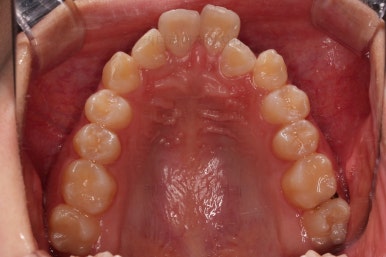

동래교정치과 초진 시의 입 안 모습이에요.

치열이 삐뚤고 덧니가 보이네요.

이번 환자분도 스스로는 보기 싫은 이유가 첫 번째였지만 사진에서도 보시다시피 양치가 잘 안되어 치석도 많고 잇몸도 부어있는 상태였어요.

그리고 앞니들이 마모가 많이 되어 있어서 각각의 치아들이 원래 형태에서 많이 변형된 것을 볼 수 있네요.